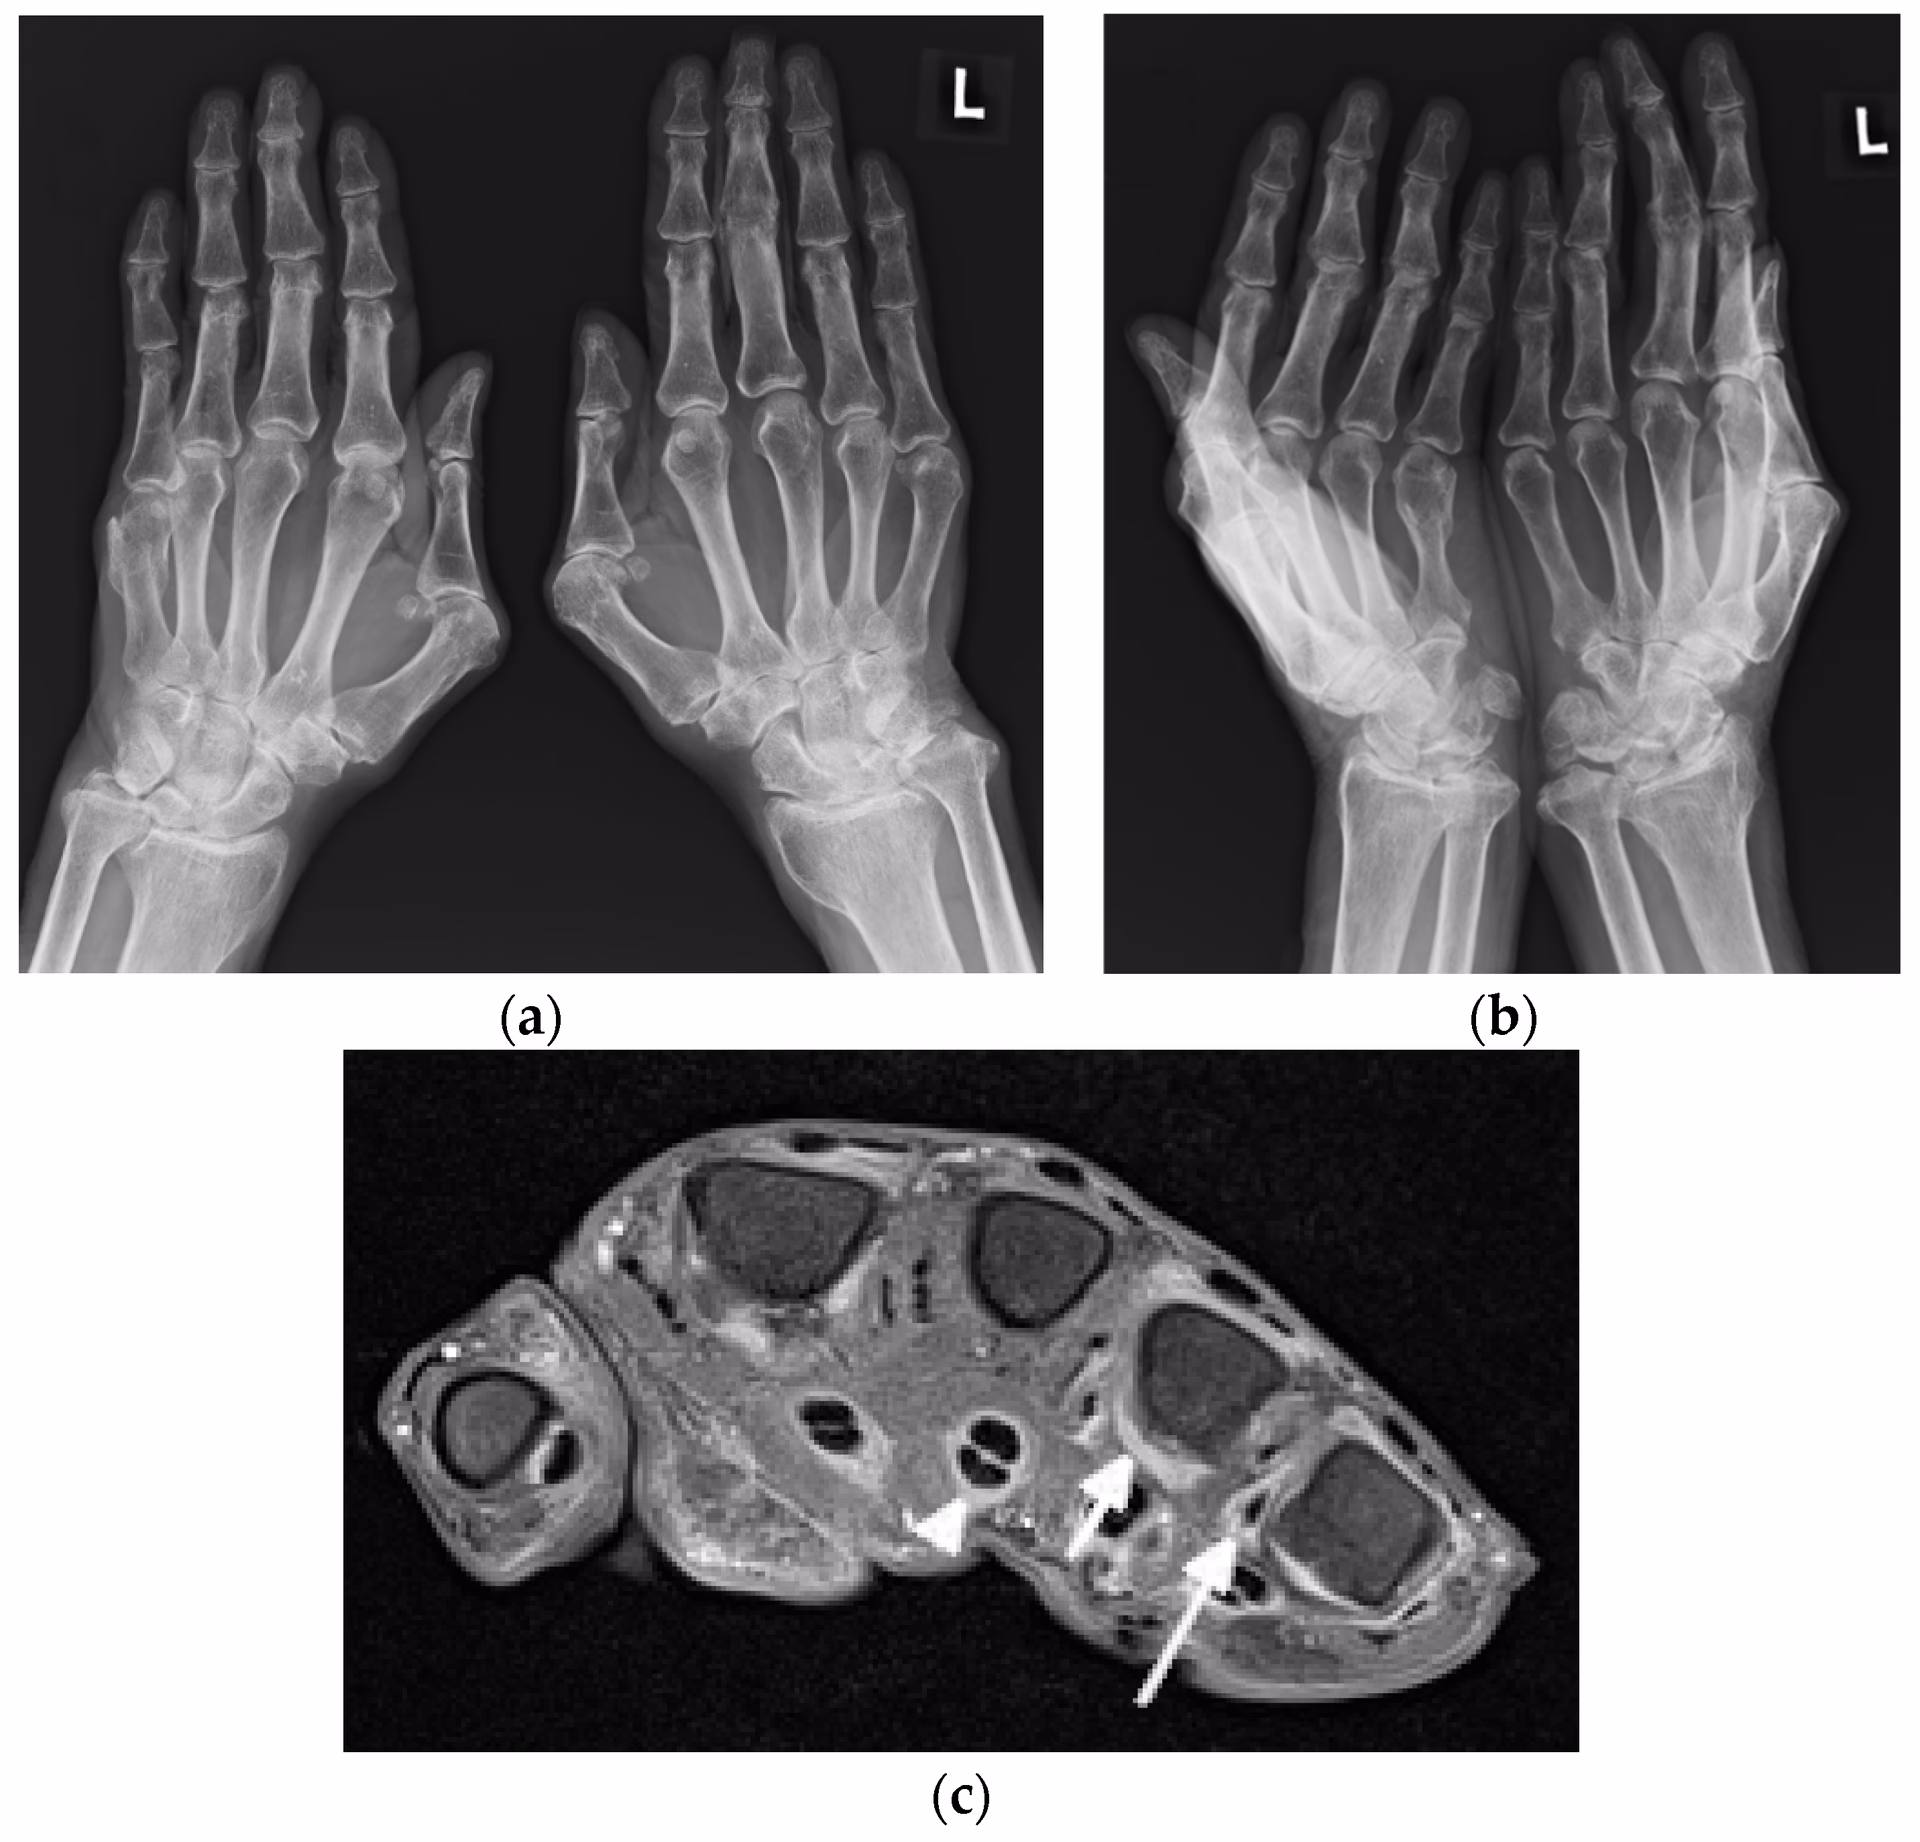

Hvad Viser Røntgenbilleder? Den Traditionelle Tilgang

Traditionelt har røntgenfotografering været det første billeddiagnostiske skridt i udredningen af ledsmerter hos lupuspatienter. Selvom røntgenbilleder kan være helt normale i de tidlige stadier af sygdommen, kan de over tid afsløre en række karakteristiske forandringer.

En undersøgelse af røntgenbilleder af hænderne hos 59 SLE-patienter viste, at mere end halvdelen (34 patienter) havde synlige abnormiteter. De mest almindelige fund var:

- Periartikulær bløddelshævelse: Hævelse i vævet omkring leddene.

- Demineralisering: En reduktion i knogletætheden omkring leddene, også kendt som periartikulær osteopeni.

Andre, mindre hyppige, men signifikante fund inkluderede:

- Fejlstillinger: Subluksation (delvis forskydning) af led, som ses ved Jaccouds artropati.

- Akral sklerose: En fortykkelse af knoglen i de yderste fingerled.

- Avaskulær nekrose: Knogledød forårsaget af nedsat blodforsyning, hvilket kan være en komplikation til både sygdommen og behandlingen med steroider.

- Bløddelsforkalkning: Aflejringer af kalcium i bløddelene omkring leddene.

- Terminal tuft resorption: En nedbrydning af knoglen i fingerspidserne.

Det er interessant, at studier har vist, at sværhedsgraden af disse radiografiske fund ikke nødvendigvis korrelerer med markører for sygdomsaktivitet i blodet, såsom lave komplementniveauer. Dette understreger, at ledsygdom ved lupus kan have sin egen dynamik, uafhængigt af den systemiske inflammation.

MR-scanning: Det Ultimative Værktøj til Detaljer

MR-scanning (Magnetisk Resonans) giver den mest detaljerede visualisering af alle strukturer i et led – knogler, brusk, ledhinder, sener og ledbånd. Dens største fordel i forbindelse med lupusgigt er evnen til at påvise knoglemarvsødem (Bone Marrow Edema - BME). Knoglemarvsødem er en væskeansamling inde i knoglen, som er et stærkt tegn på aktiv inflammation og ofte en forløber for udviklingen af knogleerosioner. MR-scanning er også overlegen til at kortlægge det fulde omfang af synovitis og tenosynovitis og kan opdage erosioner, som selv ultralyd kan overse. Studier har fundet knoglemarvsødem i håndleddet hos 13% til 35% af SLE-patienter.